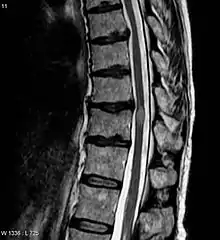

Transverse myelitis

An MRI showing a transverse myelitis lesion, which is lighter, oval shape at center-right. The patient recovered 3 months later.